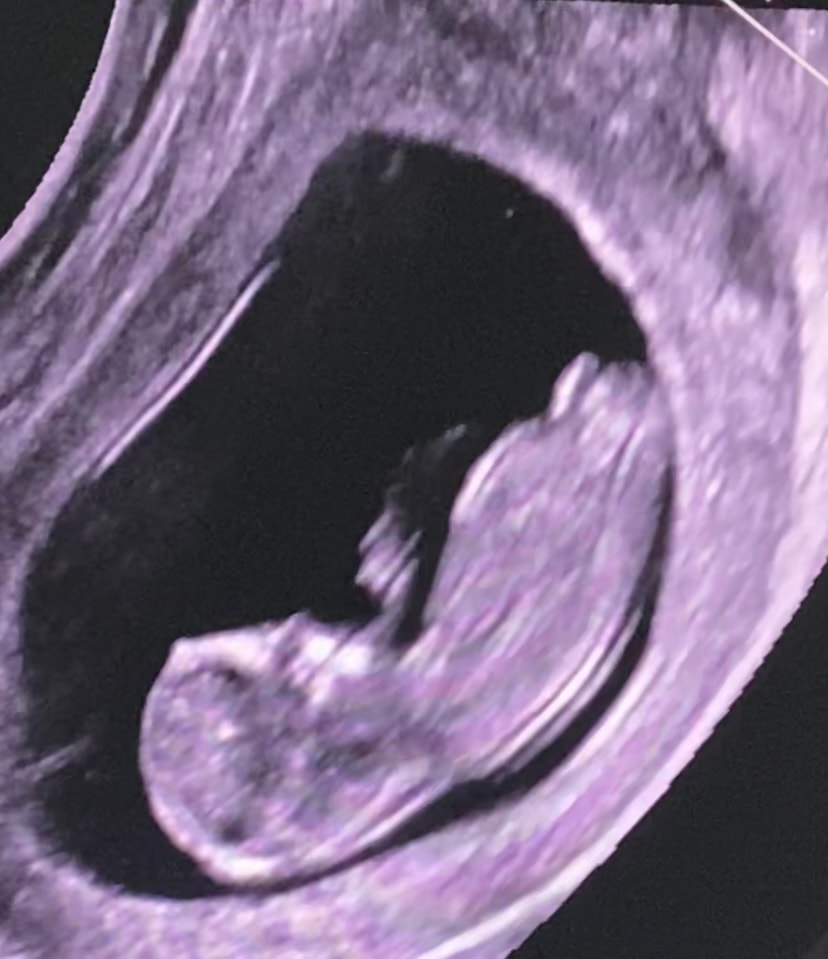

1 скрининг🍼 Половой бугорок.

Была на узи, предположительно сказали что будет девочка, надеюсь что врач не ошибся🩰

может кто разбирается, или есть фото узи своих деток на сроке 12-13 недель с точным определением пола🍬

Девочка. Не по бугорку, врач меня по полосочке вдоль позвоночника учил определять))

Доброго дня 🌸Очень вероятно ,что будет девочка 😍 Половой бугорок лежит параллельно спинке ,это предполагает женский пол ребенка 😊